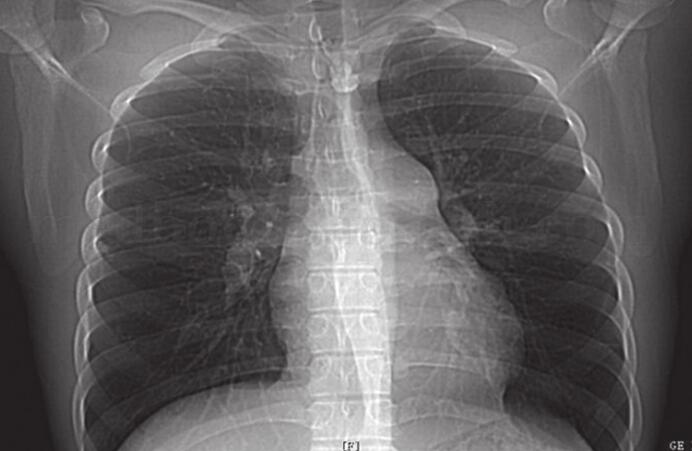

1小时条评论患者,女,21岁。因反复咳嗽、心悸、气短入院,经查体,诊断为肺动脉高压。经了解,患者于1年前出现手指雷诺现象,容易脱发,患者患肺动脉高压是否有其他原因? 【临床资料】 患者,女,21岁。因反复咳嗽7个月,活动后心悸、气短1个月入院。患者7个月前出现咳嗽,...

1小时条评论患者,女,21岁。因反复咳嗽、心悸、气短入院,经查体,诊断为肺动脉高压。经了解,患者于1年前出现手指雷诺现象,容易脱发,患者患肺动脉高压是否有其他原因? 【临床资料】 患者,女,21岁。因反复咳嗽7个月,活动后心悸、气短1个月入院。患者7个月前出现咳...